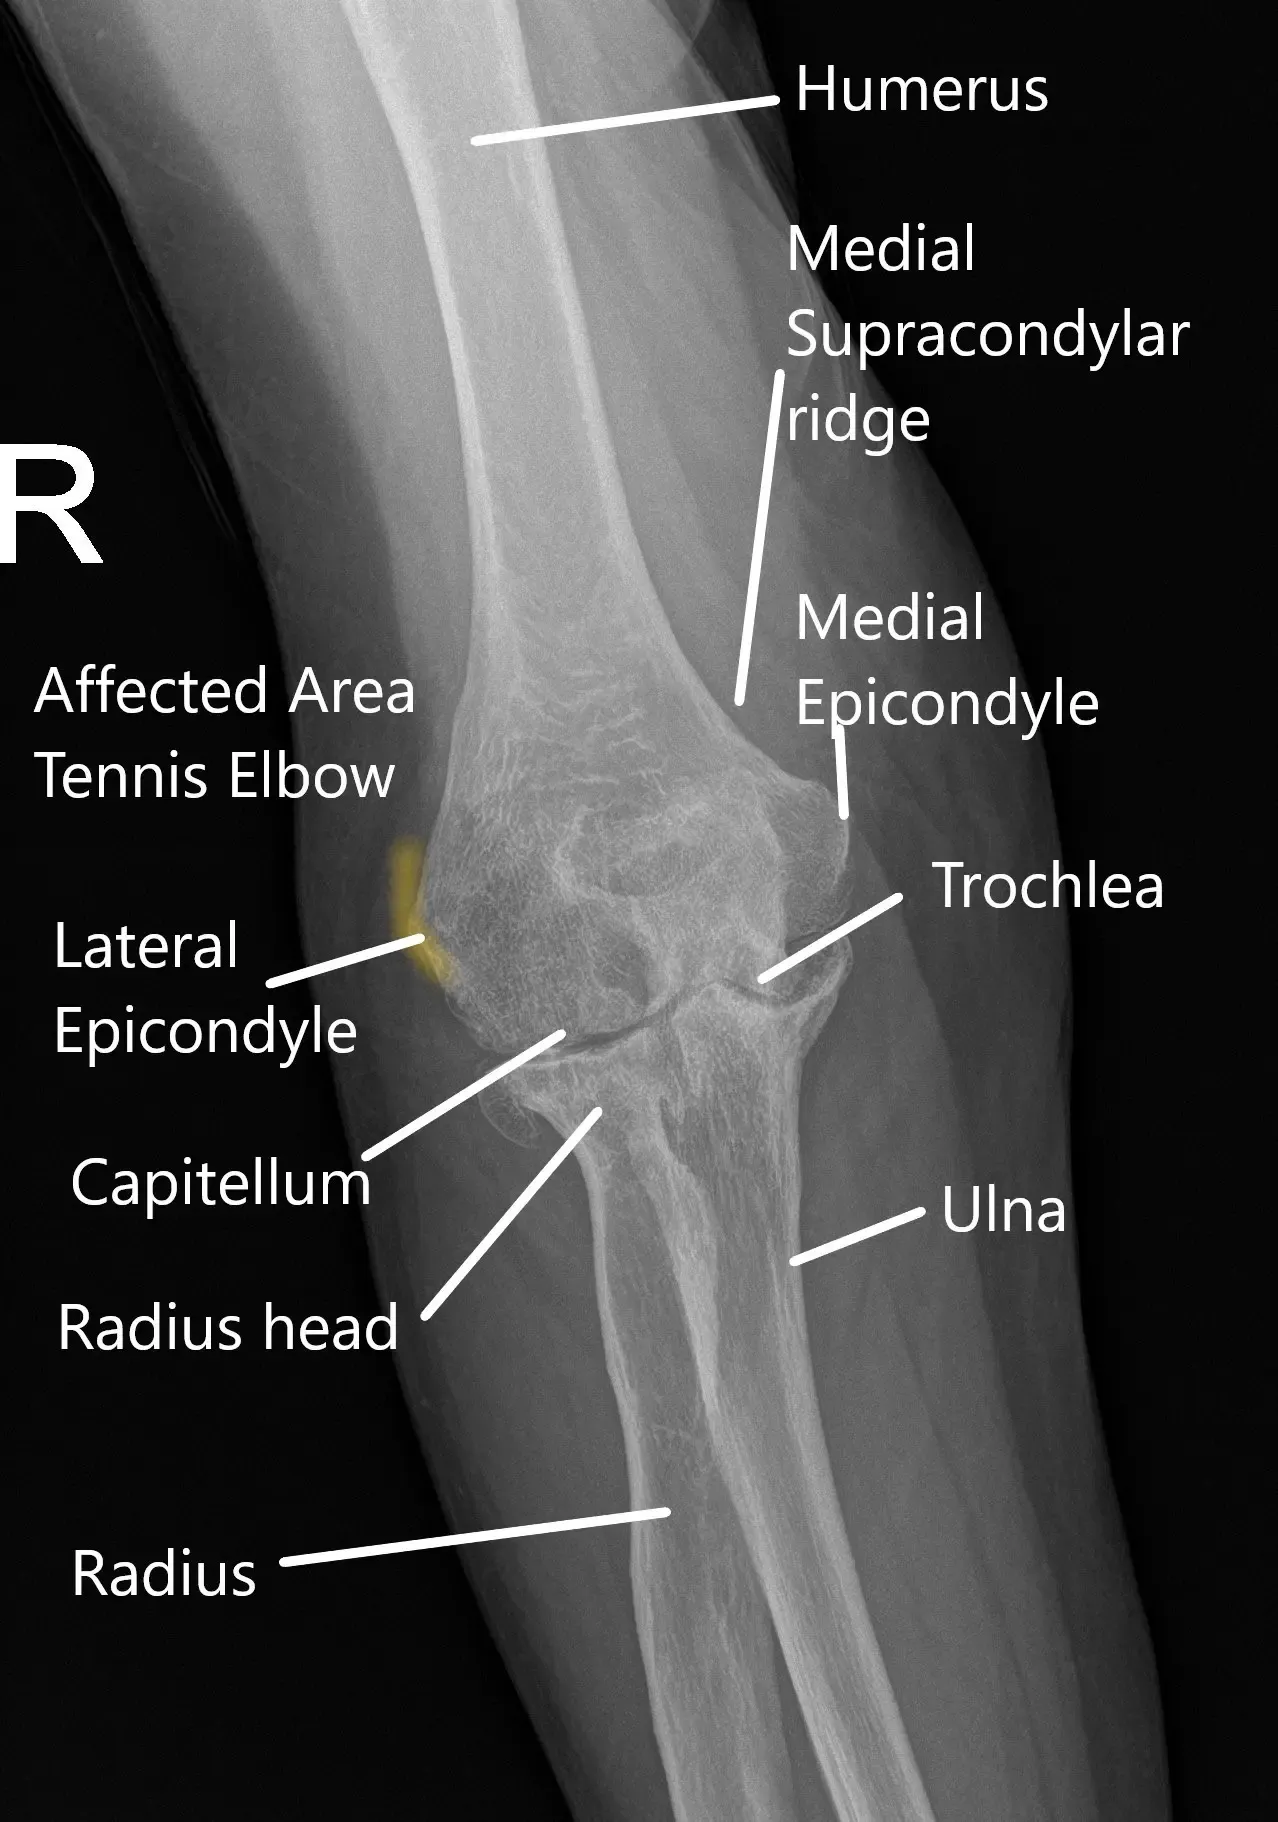

La articulación del codo se forma entre el extremo inferior del hueso del brazo y el extremo superior de los dos huesos del antebrazo. El hueso del brazo se conoce como húmero y los dos huesos del antebrazo como radio y cúbito. Diversos músculos, tendones y ligamentos estabilizan la articulación. Hay pequeños bultos óseos en el interior y el exterior del codo conocidos como epicóndilos.

El bulto en el lado exterior se conoce como epicóndilo lateral. Los músculos del antebrazo que se utilizan para estirar la muñeca y los dedos están unidos al epicóndilo lateral. Los músculos se unen al hueso a través de tendones.

Radiografía del codo en la vista AP.